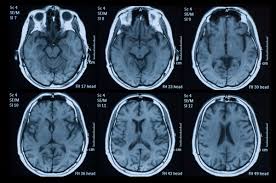

"The two biggest areas that might be done more than they should are imaging for low back pain and imaging for headaches," Callaghan said. "It's a big problem and it costs a lot of money -- we're talking a billion dollars a year on just headache imaging."

"Ordering an MRI for a headache is very quick, and it actually takes longer to describe to the patient why that's not the best route," Callaghan said. "These guidelines are meant for physicians and patients both, to trigger a conversation."